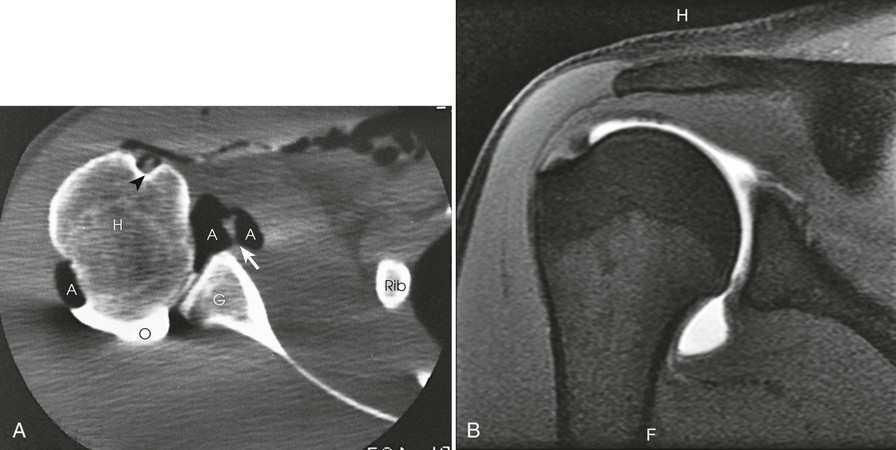

After double-contrast shoulder arthrography is performed, computed tomography (CT) may be used to examine some patients. CT images may be obtained at approximately 5-mm intervals through the shoulder joint. In shoulder arthrography, CT has been found to be sensitive and reliable in diagnosis. Radiographs and CT scans of the same patient are presented in Figs. 12-5 and 12-9. Shoulder arthrography is increasingly performed with MRI, with injection of gadolinium contrast media into the joint capsule (Fig. 12-9, B).